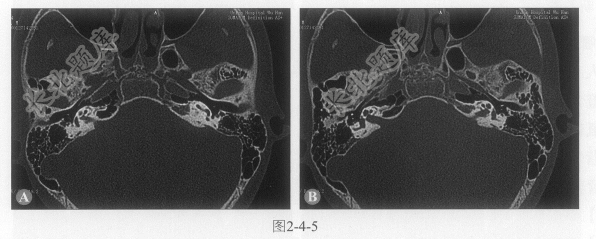

- [材料题] 患者男性,15岁,听力逐渐下降,近期感眩晕,CT图像如图2-4-5。

- 多项选择题1.病变累及的部位为:

A、双侧耳蜗周围骨质

B、窗前裂

C、前庭窗

D、半规管

E、前庭